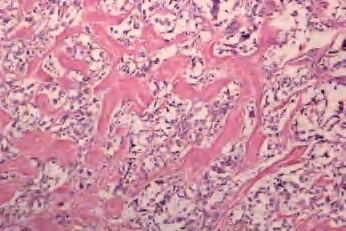

(1)滤泡亚型:由小至中等大小、不规则滤泡形成,实际上不含乳头结构,滤泡内含胶质,构成滤泡的上皮细胞有大而亮的核,含核沟和核内假包涵体。大约1/3此类肿瘤有包膜,预后与通常的乳头状癌相似(图3-44、图3-45)。

图3-44 甲状腺乳头状癌,滤泡亚型

图3-45 甲状腺乳头状癌,滤泡亚型